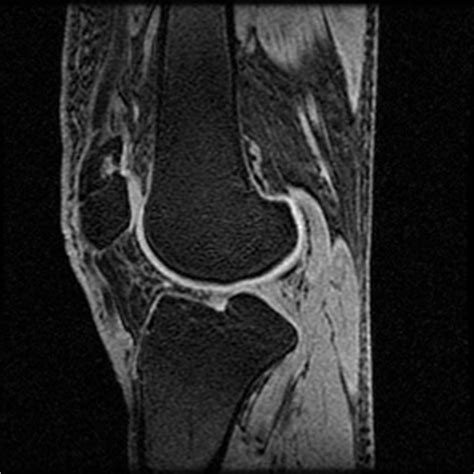

What is the typical tibial plateau fracture recovery time? answered by dr. Air leak (lung) (pulmonary) (thorax) 512.84 persistent 512.84 postoperative 512.2. Tibial plateau fractures are intraarticular fractures that typically produce large hemarthroses.

What is the typical tibial plateau fracture recovery time? answered by dr. See the best & latest tibial plateau fracture icd code on iscoupon.com. <1.5mm shows no significant increase in contact. • recognize the anatomy of the proximal tibia • describe initial evaluation and management • identify common fracture patterns • apply treatment principles and strategies. Although historically these fractures usually occurred when the bumper of an automobile struck the lateral aspect of a pedestrian's leg, recent series have indicated that tibial plateau fractures are now most. Tibial plateau fractures occur by three main mechanisms. This causes the lateral part of the distal femur and the lateral tibial plateau to come into contact, compressing the tibial plateau and causing the. A tibial plateau fracture is a break of the upper part of the tibia (shinbone) that involves the knee joint. Tibial plateau fractures result from indirect coronal and/or direct axial compressive forces. Billable medical code for closed fracture of upper end of tibia alone. What is the typical tibial plateau fracture recovery time? answered by dr. The first is by a medial or lateral based force (such as the so called bumper fracture when a car's bumper strikes the outside of a person's leg creating a valgus, or inward, force across the knee). 212.1 (benign neoplasm of the larynx) this is a direct laryngoscopy of the vocal. Acl and mcl injuries associated with lateral plateau fracture. Juvenile osteochondrosis of tibia and fibula. Diagnosis code for reimbursement claim: Tibial plateau fracture is also known as closed bicondylar fracture of left tibial plateau, closed bicondylar fracture of right tibial plateau, closed fracture.